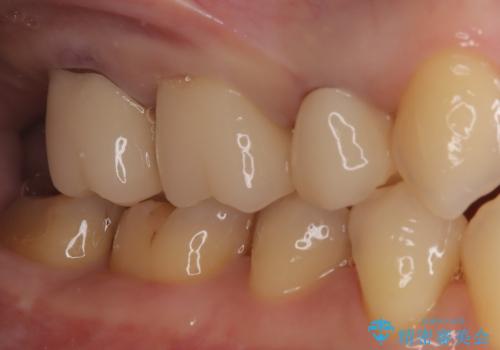

【オールセラミッククラウン】メタルフリー治療

- 古い被せ物をやり変えたいことを主訴に来院されました。

根管治療も行い、きれいな被せ物になり患者さんも喜んでいました。

3本まとめて治療をすることで来院回数を減らし、患者さんの負担を減らすことができ喜んでいただけました。